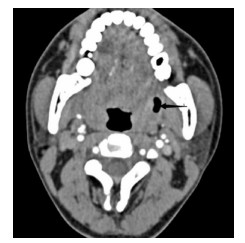

1 资料与方法患者,男,22岁,因“咽痛16 d ”于2020年6月19日就诊于浙江大学医学院附属第二医院耳鼻喉科。起初未就医,近半个月来咽痛逐渐加重,伴左侧耳朵放射痛,吞咽时明显,不能言语,伴张口困难,进食困难,夜间平卧时偶感呼吸不畅。来院前1 d,患者曾有吐出脓血性液体。查体见张口度1.5指,双侧软腭隆起,充血,双侧扁桃体Ⅱ度,右侧扁桃体后方可见少许脓液流出。急诊行颈部增强CT(图 1)示:双侧扁桃体炎伴周围脓肿形成,右侧脓腔可见积气。尝试行左侧扁桃体周围脓肿穿刺,未及明显脓液。收住入院后予头孢哌酮舒巴坦抗感染及甲泼尼龙抗炎消肿治疗,患者感咽痛逐渐缓解,软腭肿胀逐渐减轻。入院后第5天,再次行颈部增强CT(图 2)示:左扁桃体脓肿扩大,右侧扁桃体内脓肿消失,局部轻度肿胀。予行左侧扁桃体周围脓肿穿刺及切排,流出较多脓液。切排后,继续予上述药物治疗,每日定期扩张切排口,入院后第7天,切排口已无明显脓液,复查颈部增强CT(图 3)示:左侧脓肿基本吸收、残留少许气体。入院后第8天,患者予出院。后经短期随访,患者恢复情况可,无症状反复。目前患者已失随访,本研究经医院伦理委员会审批免除知情同意,批件号:(2020)伦研审第(979)号。

| 图 2 患者2020-06-25颈部C增强CT(箭头示左侧扁桃体周围脓腔扩大) |